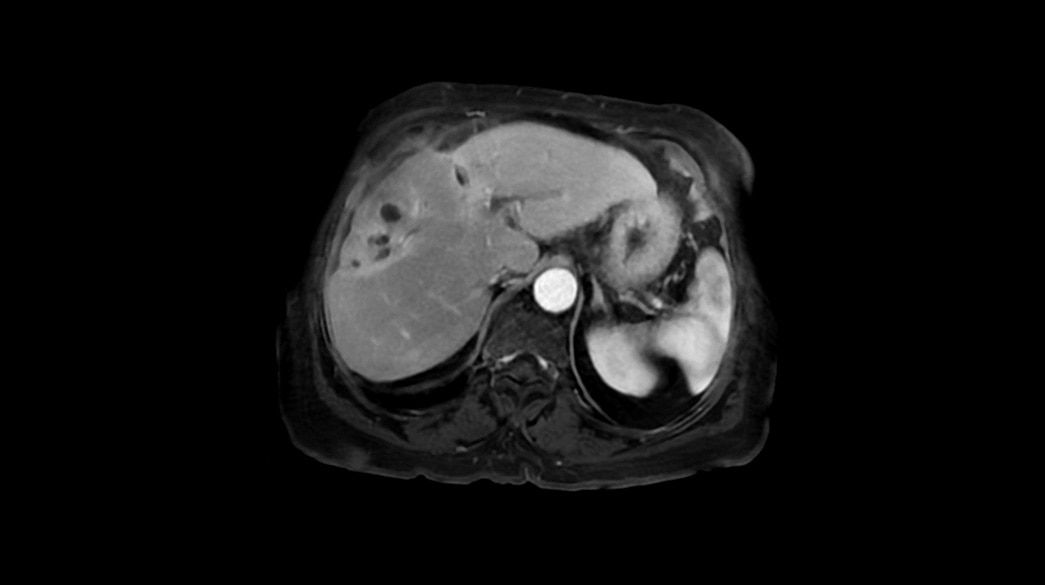

Quantifiable

Provides quantitative and actionable information

Consistent

Motion and distortion-reduced scans with high-resolution and contrast